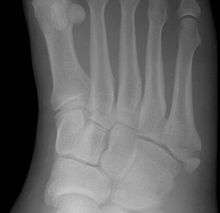

A Jones fracture is a fracture in the meta-diaphyseal junction of the fifth metatarsal of the foot.[1] The proximal end of the metatarsal, where the Jones fracture occurs, is near the midportion of the foot, on the fifth ray (of which the 5th toe belongs). Those who sustain a Jones fracture have pain over this area, swelling, and difficulty walking. The fracture was first described by orthopedic surgeon Sir Robert Jones who sustained this injury himself (while dancing) and reported it in the Annals of Surgery in 1902.[2]

A patient with a Jones fracture may not realize that a fracture has occurred. Diagnosis includes the palpation of an intact peroneus brevis tendon, and demonstration of local tenderness distal to the tuberosity of the fifth metatarsal, and localized over the diaphysis of the proximal metatarsal. Bony crepitus is unusual.

This injury should be differentiated from the developmental apophysis (5th metatarsal tuberosity) commonly and normally occurring at this site in adolescents. Differentiation is possible by characteristics such as absence of sclerosis of the fractured edges (in acute cases) and orientation of the lucent line: transverse (at 90 degrees) to the metatarsal axis for the fracture (due to avulsion pull by the peroneus brevis muscle inserting at the proximal tip) - and parallel to the metatarsal axis in the case of the apophysis. Diagnostic x-rays include anteroposterior, oblique, and lateral views and should be made with the foot in full flexion.